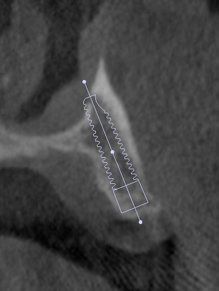

術後レントゲンです。このように斜めにインプラントをいれることにより、上顎洞への骨移植をさけることができます。これはオールオンフォーのインプラントを行っている歯科医ならではの発想です。

術前のCT右側

術前のCT左側